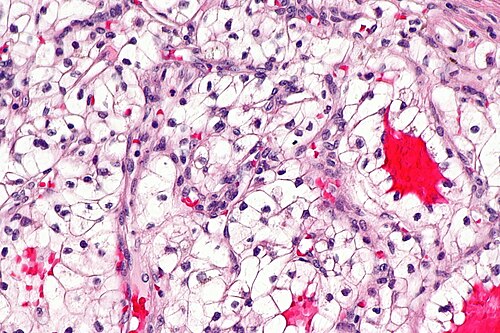

3

Diagnosis?

Clear cell renal cell carcinoma - 2 -- high mag.jpg

Angiomyolipoma

Benign kidney

Chromophobe renal cell carcinoma (classic)

Chromophobe renal cell carcinoma (eosinophilic)

Clear cell papillary renal cell carcinoma

Clear cell renal cell carcinoma

Collecting duct carcinoma

Cystic nephroma/mixed epithelial stromal tumour

HLRCC syndrome associated RCC

Hybrid oncocytic/chromophobe tumour

Metastatic carcinoma

Mucinous tubular and spindle cell carcinoma

Oncocytoma

Papillary renal cell carcinoma

Renal cell carcinoma, unclassified

Renal medullary carcinoma

Succinate dehydrogenase-deficient renal cell carcinoma

t(6;11) translocation carcinoma

Tubulocystic renal cell carcinoma

Urothelial carcinoma

Wilms tumour

Xanthogranulomatous pyelonephritis

Xp11.2 translocation carcinoma